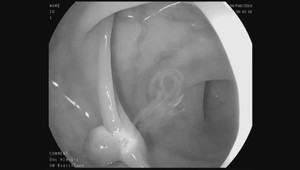

Trápi vás často pálenie záhy? Možno by ste mali spozornieť. Experti z organizácie Action Against Heartburn totiž varujú, že v niektorých prípadoch môže tento nenápadný príznak upozorňovať na jedno z najnebezpečnejších ochorení - rakovinu pažeráka.

Pálením záhy trpia v priemere 4 z 10 ľudí a vo väčšine prípadov nejde o nič závažné. Charitatívna organizácia Action Against Heartburn však upozorňuje, že môže ísť o kľúčový príznak rakoviny pažeráka. Tá býva označovaná ako „zabudnutá rakovina“ a vyskytuje sa pomerne zriedka. Podľa medzinárodných odhadov a údajov z WHO/Globocan pre krajinu v rámci Európy asi okolo 280 ľudí ročne na Slovensku dostane rakovinu pažeráka. Dlhodobo ale experti sledujú nárast tohto ochorenia.

Smrtnosť u rakoviny pažeráka dosahuje zhruba 90 percent . Problémom je najmä neskorá diagnóza. „Prognóza u tohto ochorenia je v mnohých prípadoch nepriaznivá práve preto, že rakovina pažeráka je obvykle odhalená až v pokročilom štádiu,“ uvádza Národný zdravotnícky ústav (NZIP) na svojich stránkach.